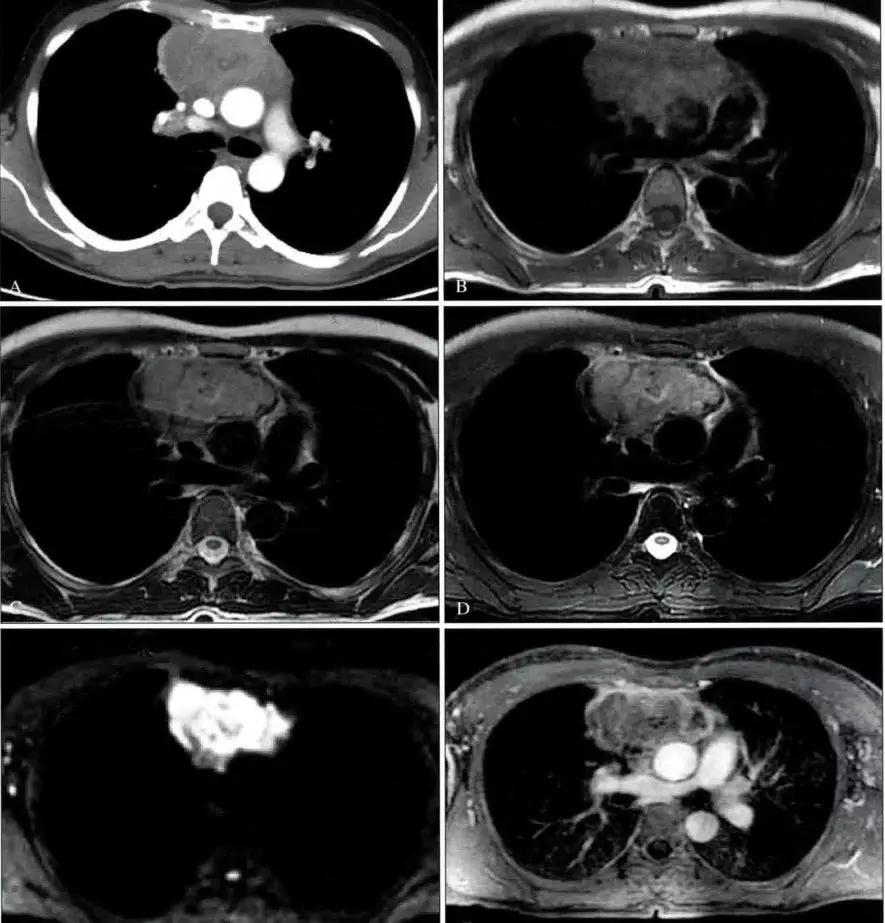

右上纵隔神经鞘瘤CT图像

a. 胸部正位片示右上纵隔脊柱旁圆形软组织密度影。b. CT平扫示右侧后上纵隔脊柱旁圆形软组织密度肿块影,密度均匀,边缘光整。c. CT增强示病灶轻度强化,密度均匀。d. CT增强矢状位重组图示肿块位于后上纵隔,与脊椎关系密切。

右中纵隔神经鞘瘤CT图像

MRI冠状位T1WI图像示胸椎右旁椭圆形病灶,病灶内部呈混杂信号,边缘呈高信号。